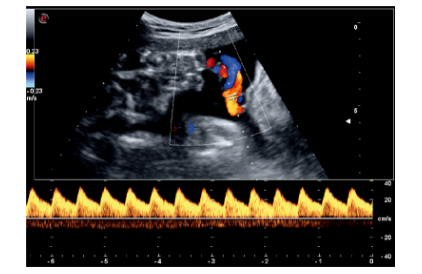

肾脏精细血流成像

脐血流频谱多普勒成像